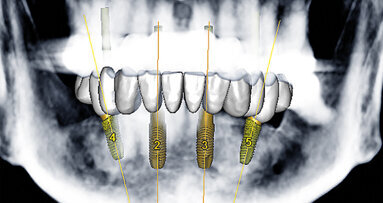

U zubu 22 bylo provedeno endodontické ošetření. Tato skutečnost podstatně omezila protetické možnosti a měla negativní efekt na prognózu zubu. Podle vývojového stadia cervikálních obratlů stanovovaného ortodontistou prostřednictvím laterálního cefalometrického rentgenologického snímku bylo odhaleno, že je možné očekávat pouze minimální transverzální a horizontální růst u této pacientky. Na základě této skutečnosti a malé protetické hodnoty pilířového zubu 22 se protetický ošetřující tým po konzultaci s pacientkou rozhodl pro celokeramický adhezivní můstek se dvěma křidélky adhezivně fixovanými na zuby 12 a 22. Cílem tohoto ošetření byl odklad implantace na tak dlouho, jak jen to bude možné, tedy do kompletního ukončení růstu mladistvé pacientky. Prostřednictvím fixní rekonstrukce tým usiloval o nejlepší možnou podporu a zachování s defektem sousedících měkkých a tvrdých tkání.

Obr. 1: Situace před ortodontickým ošetřením – adhezivní můstek s náhradou zubu 21